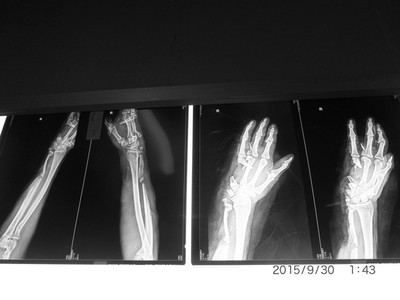

四肢创伤组织移植案例

右腹部旋髂浅动脉游离皮瓣移植

右臂皮瓣移植